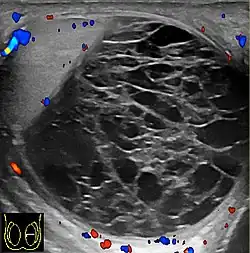

Patients with testicular lymphoma are usually old aged around 60 years of age, present with painless testicular enlargement and less commonly with other systemic symptoms such as weight loss, anorexia, fever and weakness. Bilateral testicle involvements are common and occur in 8.5% to 18% of cases. At sonography, most lymphomas are homogeneous and diffusely replace the testis [Fig. 7]. However focal hypoechoic lesions can occur, hemorrhage and necrosis are rare. At times, the sonographic appearance of lymphoma is indistinguishable from that of the germ cell tumors [Fig. 8], then the patient's age at presentation, symptoms, and medical history, as well as multiplicity and bilaterality of the lesions, are all important factors in making the appropriate diagnosis.